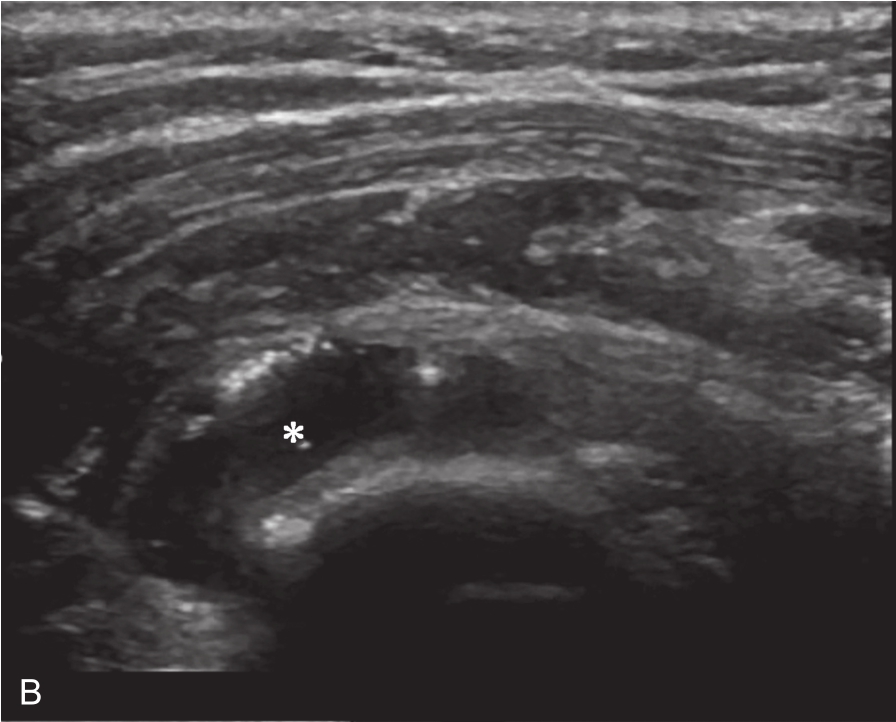

▲ 图2-6-3 超声引导下肩关节腔介入治疗超声图(一)

A、B.二维超声显示肩关节腔少量积液,滑膜增厚;C.超声引导针尖进入关节腔;D.超声示意图,虚线蓝色区域:后关节腔;单星号:腋下关节囊;双星号:后关节腔;短箭头:穿刺针;长箭头:穿刺针路径;L:盂唇;HH:肱骨头